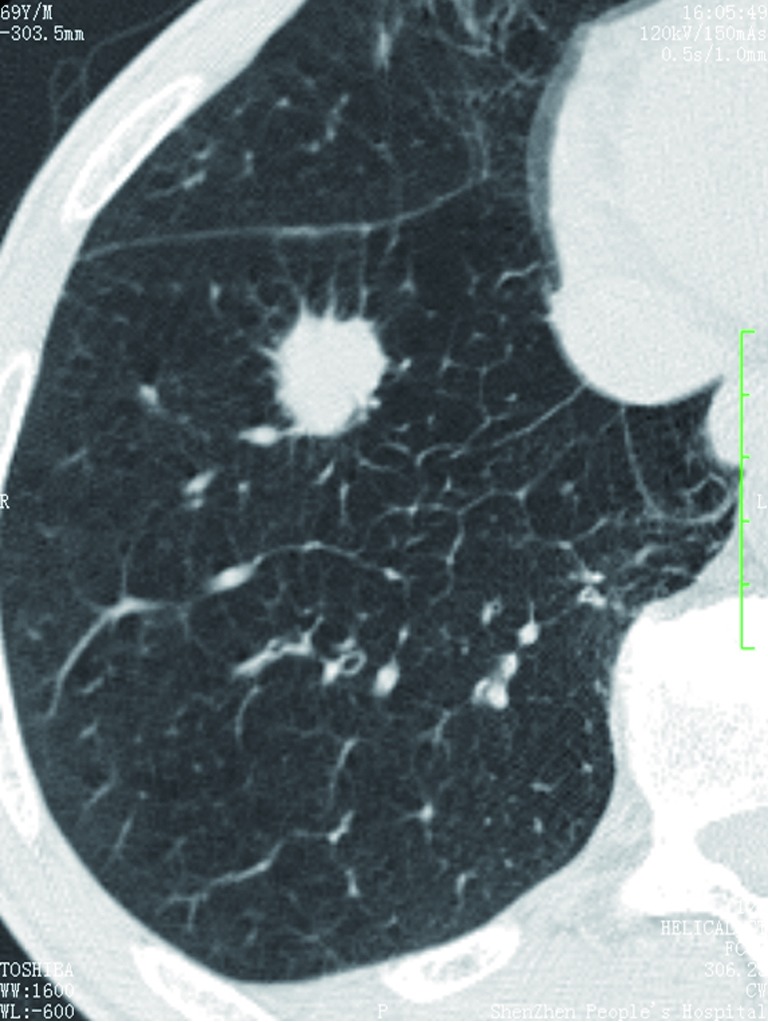

Figure 1.

CT shows a case of a small hamartoma (arrow) appearing as a non-calcification solid nodule with lobulated margin, mimics a malignant nodule.

Figure 2.

CT shows a case of hamartoma (size: 24 mm) with “popcorn” pattern calcification.